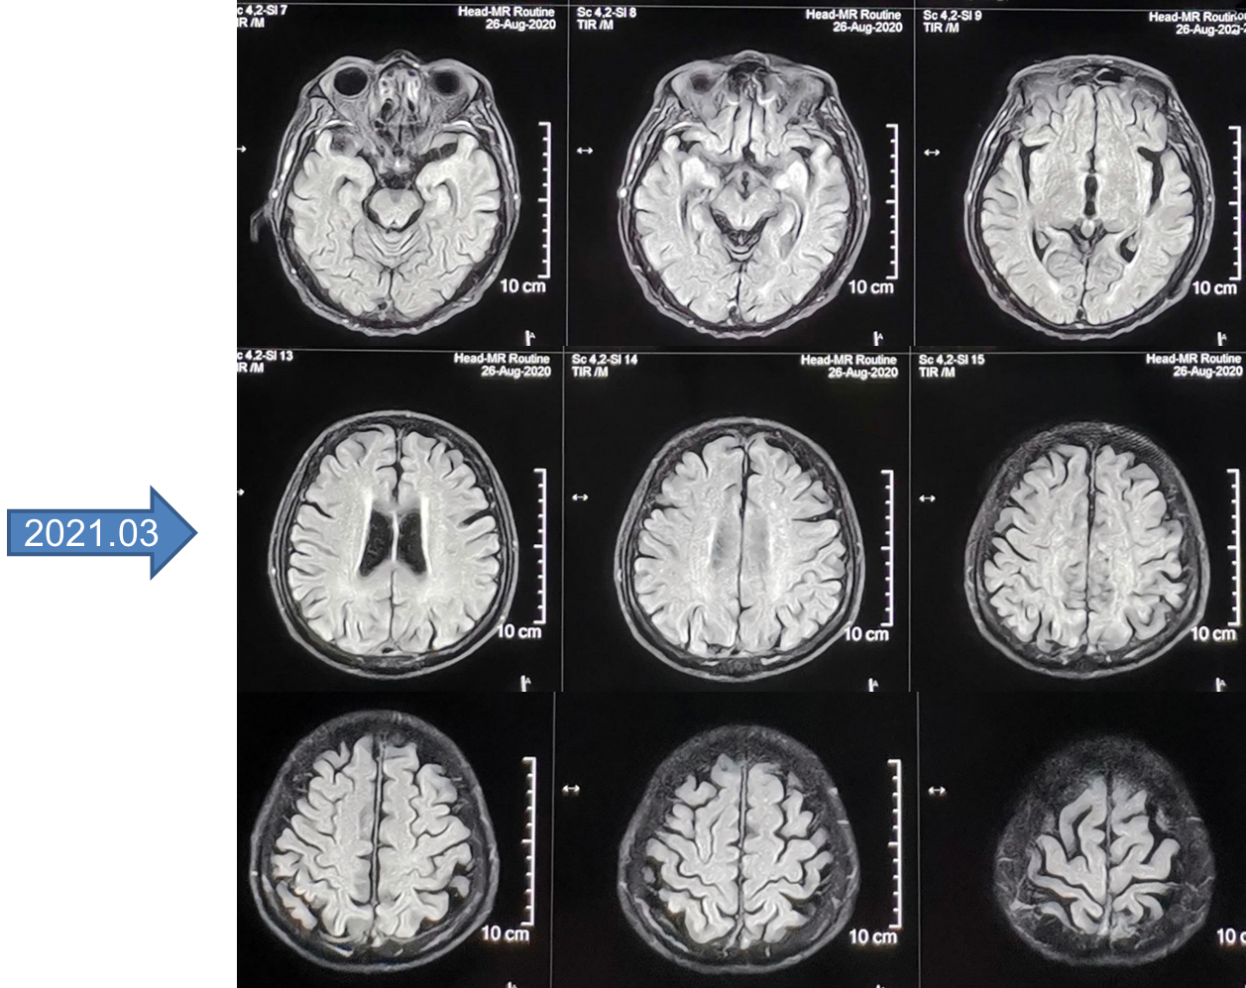

2020-01-13头部CT(图3):未见明显异常。

治疗过程中的影像学检查结果如下图:

在诊断方面,患者于外院行支气管镜活检病理提示腺鳞癌,但未系统治疗。后为求进一步诊治转入我院,经完善胸部CT、全腹CT、头颅CT等影像学检查,并结合穿刺活检、免疫组化及基因检测,最终明确诊断为原发性支气管ASC,伴右肺门、纵隔淋巴结转移,以及骨、肾上腺、胸膜、左下腹软组织等多发转移。

基于上述循证医学证据,并结合患者PD-L1高表达等病情及经济条件等因素,一线治疗给予免疫联合抗血管生成治疗。治疗过程中,复查胸部CT,可见病灶逐渐缩小。但联合治疗1年后,患者连续两次在使用ICIs后出现皮肤毒性,遂停用ICIs。此时患者病情稳定,但拒绝静脉化疗。因此,寻找一种高效、低毒且便捷的口服维持治疗方案成为临床首选。

综合考量患者的年龄、身体状况及治疗需求,临床给予长春瑞滨软胶囊节拍化疗联合恩度抗血管生成治疗。进行8个周期的联合治疗后,序贯长春瑞滨软胶囊节拍化疗长期维持。该方案取得了令人满意的成果:患者疗效持续维持PR,未出现新发转移(如颅内转移),生活质量良好。截至目前,患者已超过60个月(末次随访时间:2025年3月)未进展,为晚期ASC患者的长期生存提供了宝贵的临床经验和新的希望。